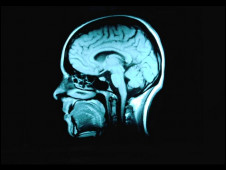

接受教育可降低患失智癥風險

科學家發現受教育時間越久,出現失智癥的機率就越低。

在過去10年當中,有關失智癥(dementia, 或稱癡呆)的各項研究一致顯示接受教育的時間越長的人,患失智癥的機會越低。

現在,英國和芬蘭的研究人員針對三個大型的有關老年化的研究進行分析,這三個大型研究一共觀察了872名已經去世的老年人的大腦。

研究人員發現,在他們去世之后,他們大腦里出現失智癥的病變,與他們接受的教育程度沒有明顯關系。

但是接受教育程度越高的人,就越能適應老年之后帶來的種種問題,包括記憶力減退。

調查顯示,每接受教育一年,失智癥發生機率就會降低11%。

劍橋大學的漢娜·基格(Hannah Keage)表示,“我們發現在人死后,有的人大腦里出現失智癥病變,但這個人生前卻沒有失智癥癥狀。”

“研究顯示,接受教育能讓人更好的適應他們大腦老化帶來的問題。”